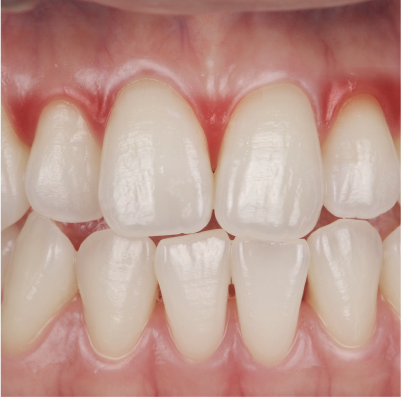

• 妊娠性エプーリスの症例写真

妊娠性エプーリス

妊娠初期から中期に、歯肉にできる腫れもののことです。触ると痛かったり、出血したりしますが、ほとんどの場合で出産後に治ります。